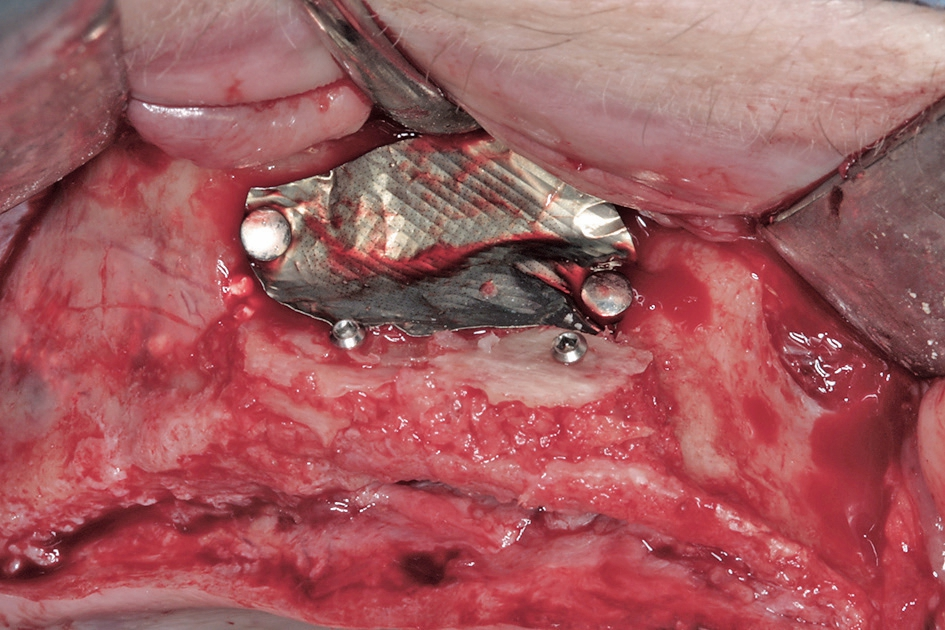

Der chirurgische Behandlungsteil bestand aus drei Eingriffen im Abstand von jeweils etwa drei Monaten. Im ersten Eingriff wurden die augmentativen Maßnahmen im atrophierten Oberkiefer (Abb. 4) nach retromolarer Knochenentnahme aus dem rechten Unterkiefer (Abb. 5 bis 7) in horizontaler und vertikaler Dimension vorgenommen. Dazu wurde der Kiefer durch das Anbringen von autologen Knochenblöcken nach dem biologischen Konzept lateral verbreitert. Mittels der Schalentechnik werden dabei die Blöcke auf Distanz gesetzt und der Zwischenraum mit autologen Knochenpartikeln gefüllt (Abb. 8 und 10). Durch die Partikulierung des Knochens wird die Oberfläche vergrößert und es kann eine bessere Revaskularisierung des augmentierten Bereichs erfolgen [5].

Zudem war beidseitig eine Sinusbodenelevation notwendig (Abb. 9), die mittels lateralen Zugangs durchgeführt wurde. Eine entstandene Perforation wurde vernäht und mit einer Kollagenmembran abgedeckt (Abb. 11). In der sogenannten Schichttechnik werden bei der Sinuselevation im kaudalen Bereich autologe Knochenpartikel eingebracht, so dass die Implantate später etwa 10 mm im Eigenknochen stehen. Im kranialen Bereich wird langsam resorbierendes Knochenersatzmaterial (Symbios®, DENTSPLY Sirona, Mannheim) eingebracht. Diese dünne Schicht Biomaterial schützt vor Resorptionen durch den Druck in der Kieferhöhle. Auch auf der linken Seite des Oberkiefers wurde der Kieferkamm lateral augmentiert (Abb. 12 und 13). Das Konzept der Schichttechnik beim Sinuslift dient der Verkürzung der Behandlungszeit, so dass die Implantate schon nach einem früheren Zeitpunkt inseriert werden können. Die Insertion der Implantate ist nach dem hier vorgestellten Konzept bereits nach drei bis vier Monaten möglich im Vergleich zu 7 bis 8,5 Monaten beim Einsatz von reinem Biomaterial und gleichzeitiger geringer Restknochenhöhe [13]. Die Abdeckung des Sinusfensters erfolgte mit einer nicht resorbierbaren Membran aus Reintitan (FRIOS® BoneShield, DENTSPLY Implants, Mannheim) bevor der Verschluss des augmentierten Bereiches durch den Mukoperiostlappen erfolgt.